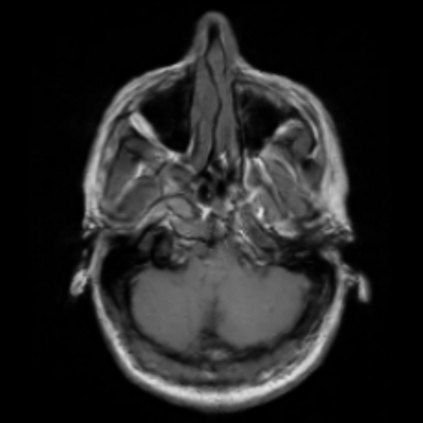

Motion artifacts are a primary source of magnetic resonance (MR) image quality deterioration with strong repercussions on diagnostic performance. Currently, MR motion correction is carried out either prospectively, with the help of motion tracking systems, or retrospectively by mainly utilizing computationally expensive iterative algorithms. In this paper, we utilize a novel adversarial framework, titled MedGAN, for the joint retrospective correction of rigid and non-rigid motion artifacts in different body regions and without the need for a reference image. MedGAN utilizes a unique combination of non-adversarial losses and a novel generator architecture to capture the textures and fine-detailed structures of the desired artifacts-free MR images. Quantitative and qualitative comparisons with other adversarial techniques have illustrated the proposed model's superior performance.

翻译:移动文物是磁共振(MR)图像质量恶化的一个主要来源,对诊断性能产生强烈影响。目前,MR运动的校正要么是预期性的,借助运动跟踪系统,要么是追溯性的,主要是利用成本昂贵的计算迭代算法。在本文中,我们使用名为MedGAN的新颖的对抗性框架,联合追溯性地校正不同身体区域的硬性和非硬性运动文物,而不需要参考图像。 MedGAN利用非对抗性损失和新型生成器结构的独特组合来捕捉无MR图象的纹理和精细详细结构。 与其他对抗性技术的定量和定性比较展示了拟议模型的优异性表现。